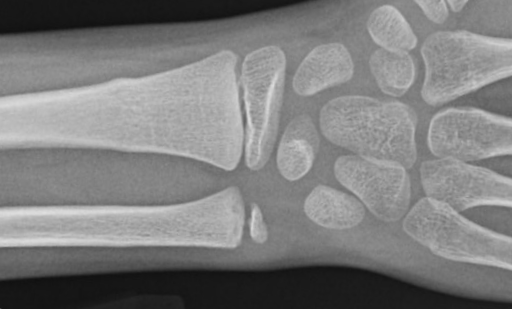

These are “non-displaced” fractures of the third and fourth metacarpals - the long bones of your hand.